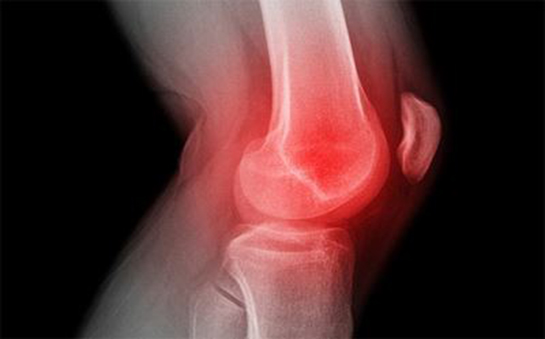

Boyun kaymasının belirtileri arasında boyun ağrısı, baş dönmesi, sinir sıkışması gibi durumlar yer alabilir. Eğer tedavi edilmezse, bu sorunlar uzun vadede daha ciddi sağlık problemlerine yol açabilir. Bu nedenle, bu konuda bilgi sahibi olmak, erken teşhis ve tedavi için oldukça önemlidir.

Kayma durumunu yaşamak gerçekten zor bir deneyim olmalı. Özellikle disk kayması gibi durumlar, sıradan günlük aktiviteleri bile zorlaştırabilir. Belirtilerinin bacaklarda ağrı, karıncalanma ve uyuşma gibi rahatsız edici şeyler olduğunu düşününce, bu durumla başa çıkmanın ne kadar zor olabileceğini anlayabiliyorum. Aynı şekilde çene kayması da günlük yaşantıyı etkileyebilir. Konuşurken zorlanmak veya ağzı tam kapatamamak, sosyal ilişkileri bile etkileyebilir. Diz kayması ise, özellikle spor yapanlar için ciddi bir tehlike oluşturabilir. Burun kayması da, hem fiziksel hem de estetik açıdan sorun yaratabilir. Tüm bu kayma türleri, dikkat edilmesi gereken ciddi sağlık sorunları. Böyle bir durumla karşılaşanlar için en kısa sürede bir uzmana görünmenin ne kadar önemli olduğunu düşünüyorum. Peki, bu tür durumlarda tedavi süreci nasıl işliyor, merak ediyorum.

Tafte, kayma durumları gerçekten de yaşam kalitesini olumsuz etkileyen önemli sağlık sorunlarıdır. Disk kayması, çene kayması, diz kayması gibi durumlar hem fiziksel hem de psikolojik açıdan kişiyi zorlayabilir. Belirttiğin gibi, bu tür sorunlar gündelik yaşamı etkileyerek sosyal ilişkileri bile olumsuz yönde etkileyebilir.